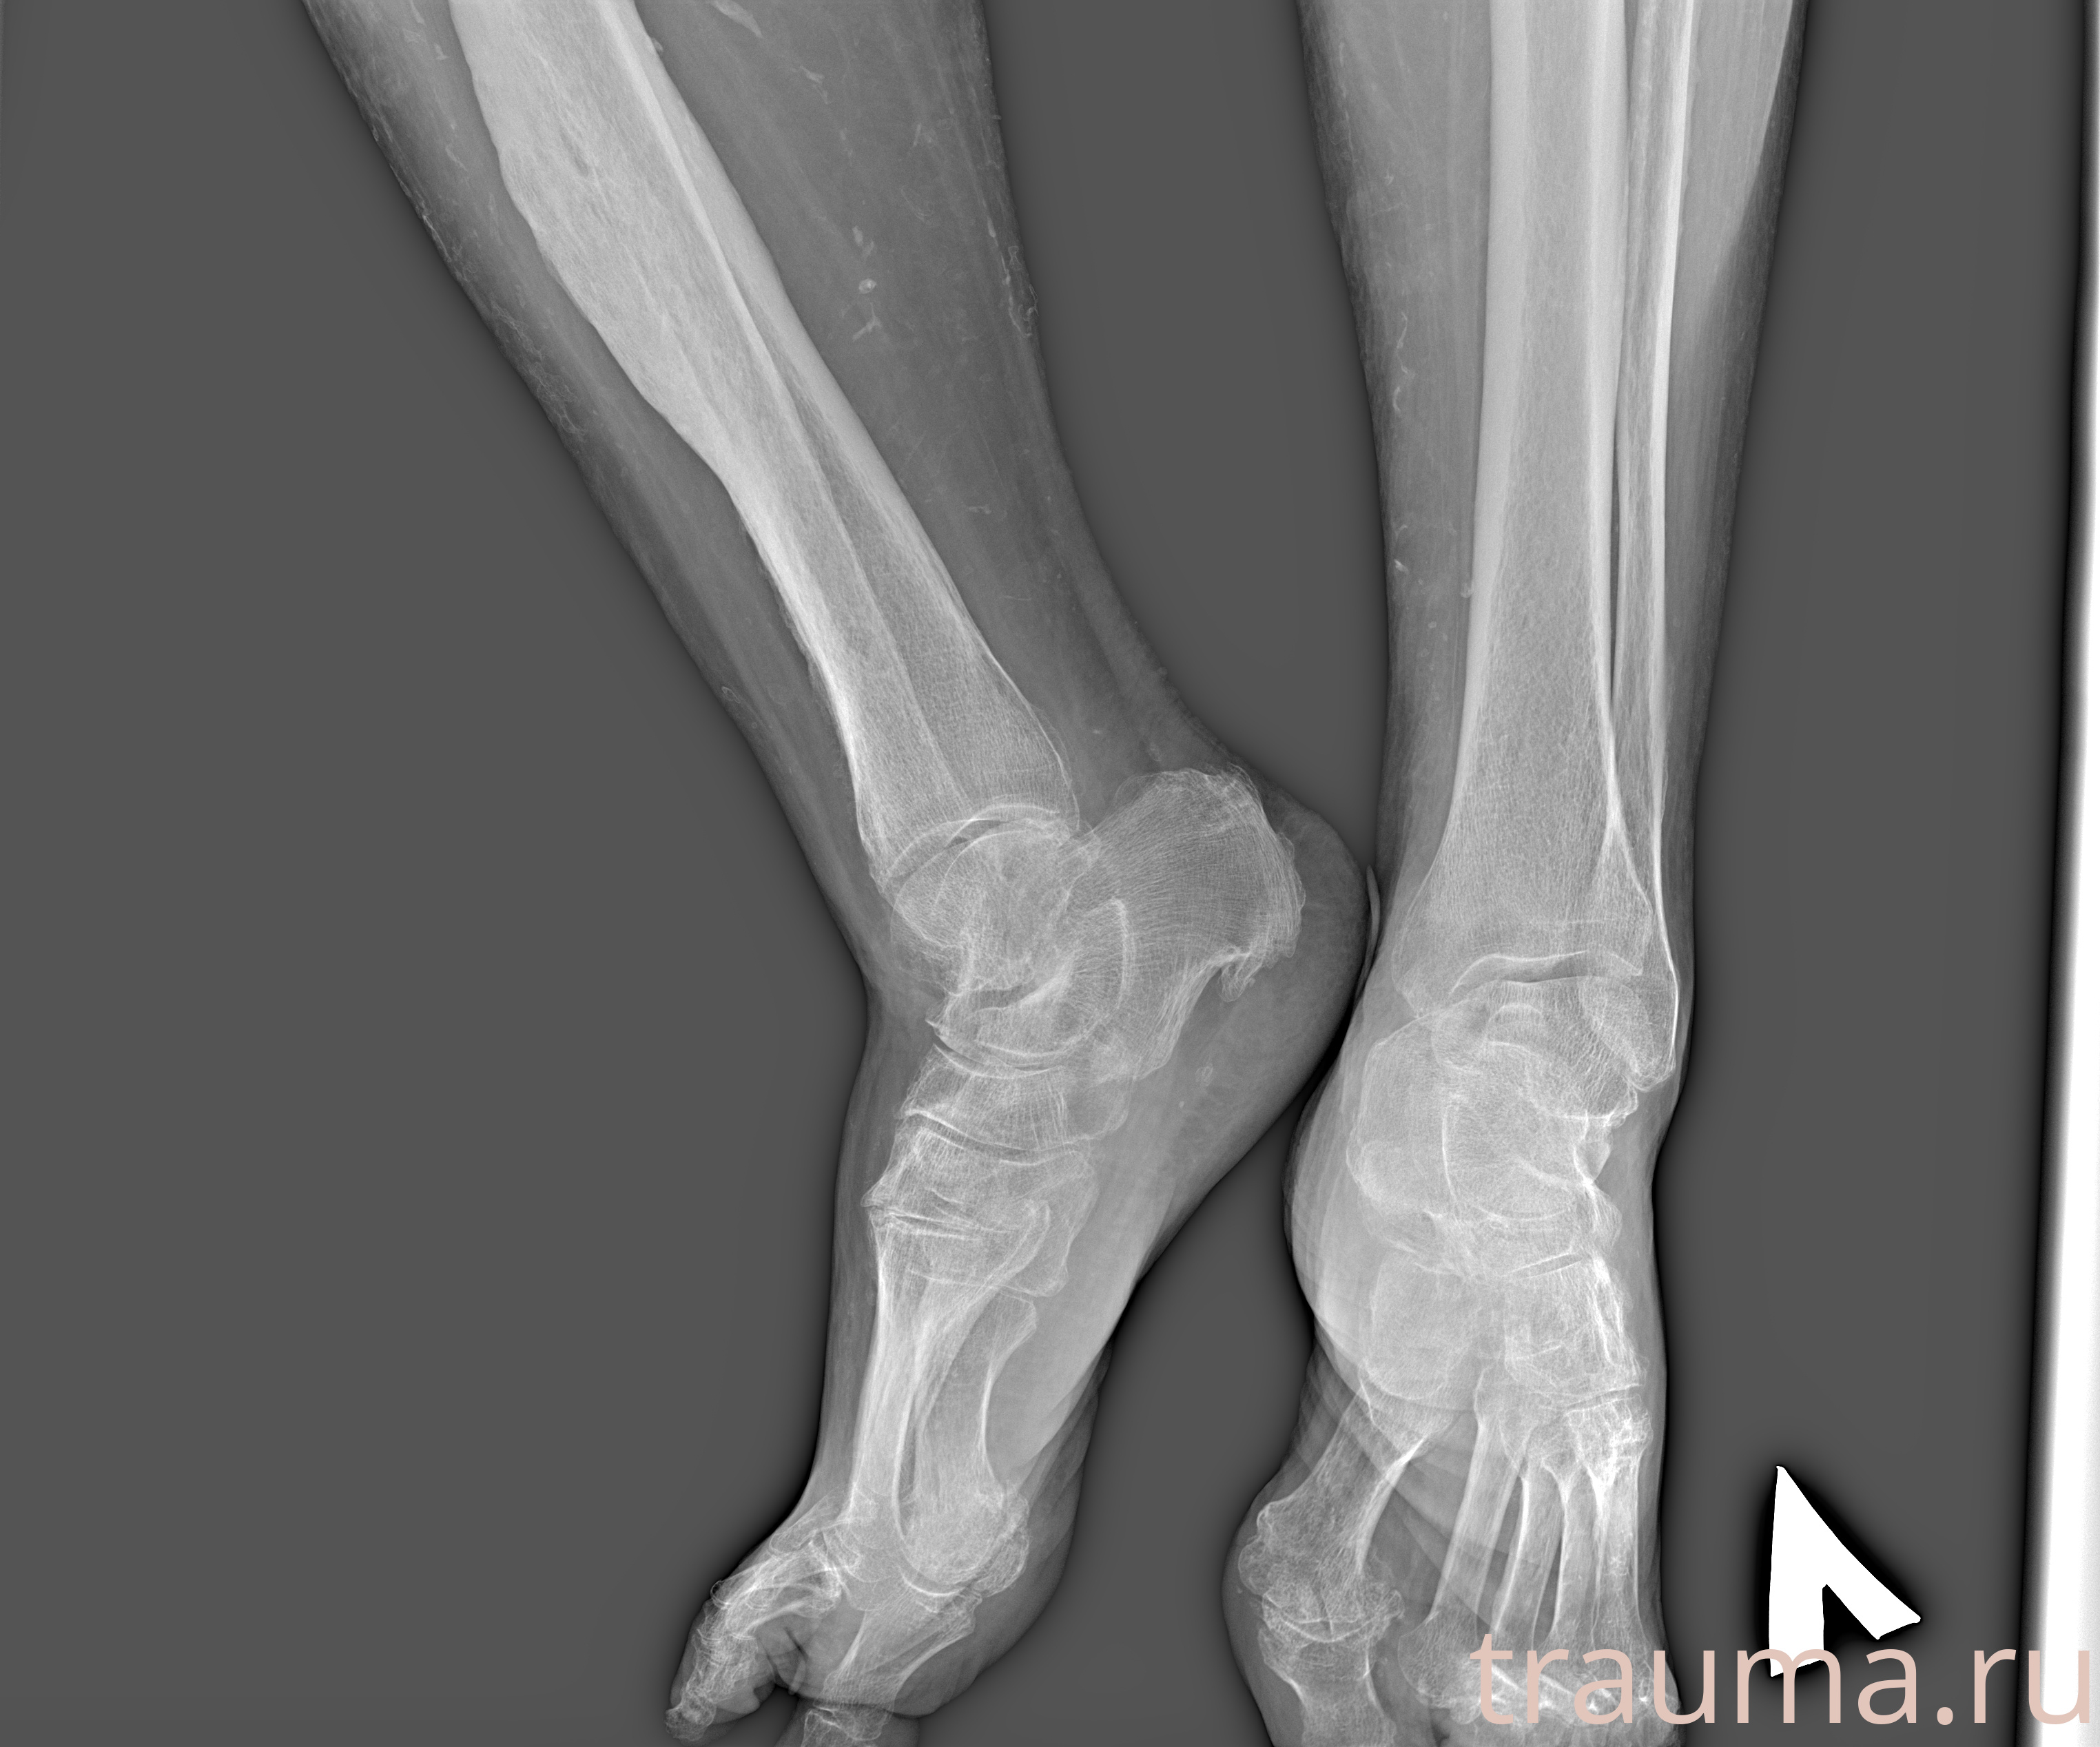

Рентген на дому: по вашему адресу приезжает врач-рентгенолог, травматолог-ортопед с мобильным рентгеновским аппаратом, проводит диагностику травмы или заболевания, делает необходимые рентгенограммы, дает рекомендации по дальнейшему лечению. Получить качественные снимки в домашних условиях возможно благодаря уникальной методике, разработанной МосРентген Центром для института  Склифосовского